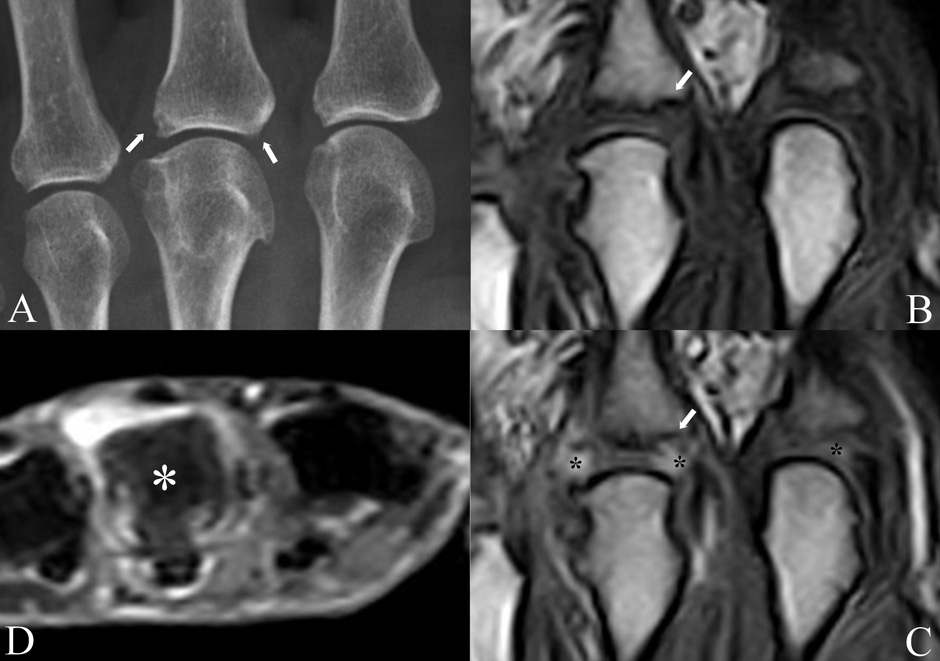

Figure 1

Conventional radiography and MRI study of the metacarpophalangeal joints of a patient with undifferentiated oligoarthritis lasting from less than 6 months. A) the radiogram shows degenerative changes (osteophytes) of the 3rd metacarpophalangeal head and small erosions (arrows) of the proximal end of the corresponding phalanx. The erosion on the right is only suspected because of an interrupted bony cortex; pre (B) and post-contrast (C) coronal Turbo 3D MRI sequences showing synovial enhancement of the painful 3rd metacarpophalangeal joint (asterisks) and confirmation of the suspected erosion (arrow). Inflammation is present also in the asymptomatic and clinically normal 2nd metacarpophalangeal joint (asterisk). Axial STIR MRI sequence (D) showing intense bone marrow oedema of the 3rd metacarpal head (asterisk), which appears gray in comparison with the normal bone of the other metacarpals, which appears black. All MRI images are obtained with an extremity-dedicated 0.2 T machine (Esaote, Genova, Italy).

Early diagnosis of arthritis can be facilitated by showing synovial inflammation, defined as synovial fluid effusion, neoangiogenesis, and vasodilatation, in painful but otherwise clinically normal or only doubtful joints [5]. This can be achieved by both Doppler US [6] and contrast-enhanced MRI [7] (fig. 1B, C). In addition, MRI can show an early inflammatory bone lesion characterised by oedema (fig. 1D), which is a potent predictor of disease progression [8] and radiographic erosions. Bone marrow oedema (BME) is best seen on fat-suppressed or STIR sequences. US and MRI could represent a useful adjunct to the 1987 ACR classification criteria for RA [9] because they often identify subtle levels of inflammation even in asymptomatic joints, which facilitates reaching the minimum number of criteria required for diagnosis. Despite its advantages, imaging has been not included in the new 2010 criteria for RA [10], probably because of erratic availability of these techniques. Nonetheless, most tertiary referral rheumatological centres today routinely use advanced imaging to corroborate diagnosis in patients who present early.